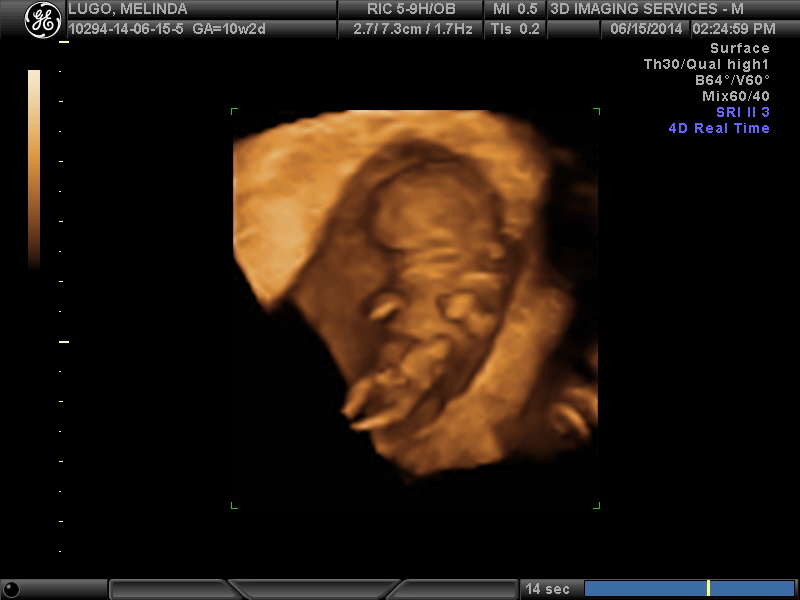

During the scan, we found out so much information, it really was amazing to see the baby move, and the beating heart. We learned that previous suspicions of a vanishing twin were most likely correct as there was a circle around the viewable babys gestational sac. 1 baby was definitely confirmed according to the 2 techs in the room with us. THe baby's placents is in the front, so ramzi theory wont work for us, right?

During the scan i noticed the techs whisper to eachother and chuckle, and I had asked if they could get me a nub shot and that caused them to giggle as they asked, "So i do see something, although its very early, so if you are interested in knowing the gender..."

Although we would happily welcome a healthy baby of either gender, i must confess that i am hard core wishing for a boy! The tech (18 years of experience) said that she wasnt planning on saying anything, but that it was just so prominent that it was even noticeable in the 2d scan, she has a VERY strong "feeling" that the baby is a BOY!!!

She urged us to keep this quiet, and not go out buying anything just yet, BUT that she would be thoroughly shocked if the baby werent a boy. She says with the nub rising at such angle already and the bulbous end to the turbucle, its very very BOY-ish.